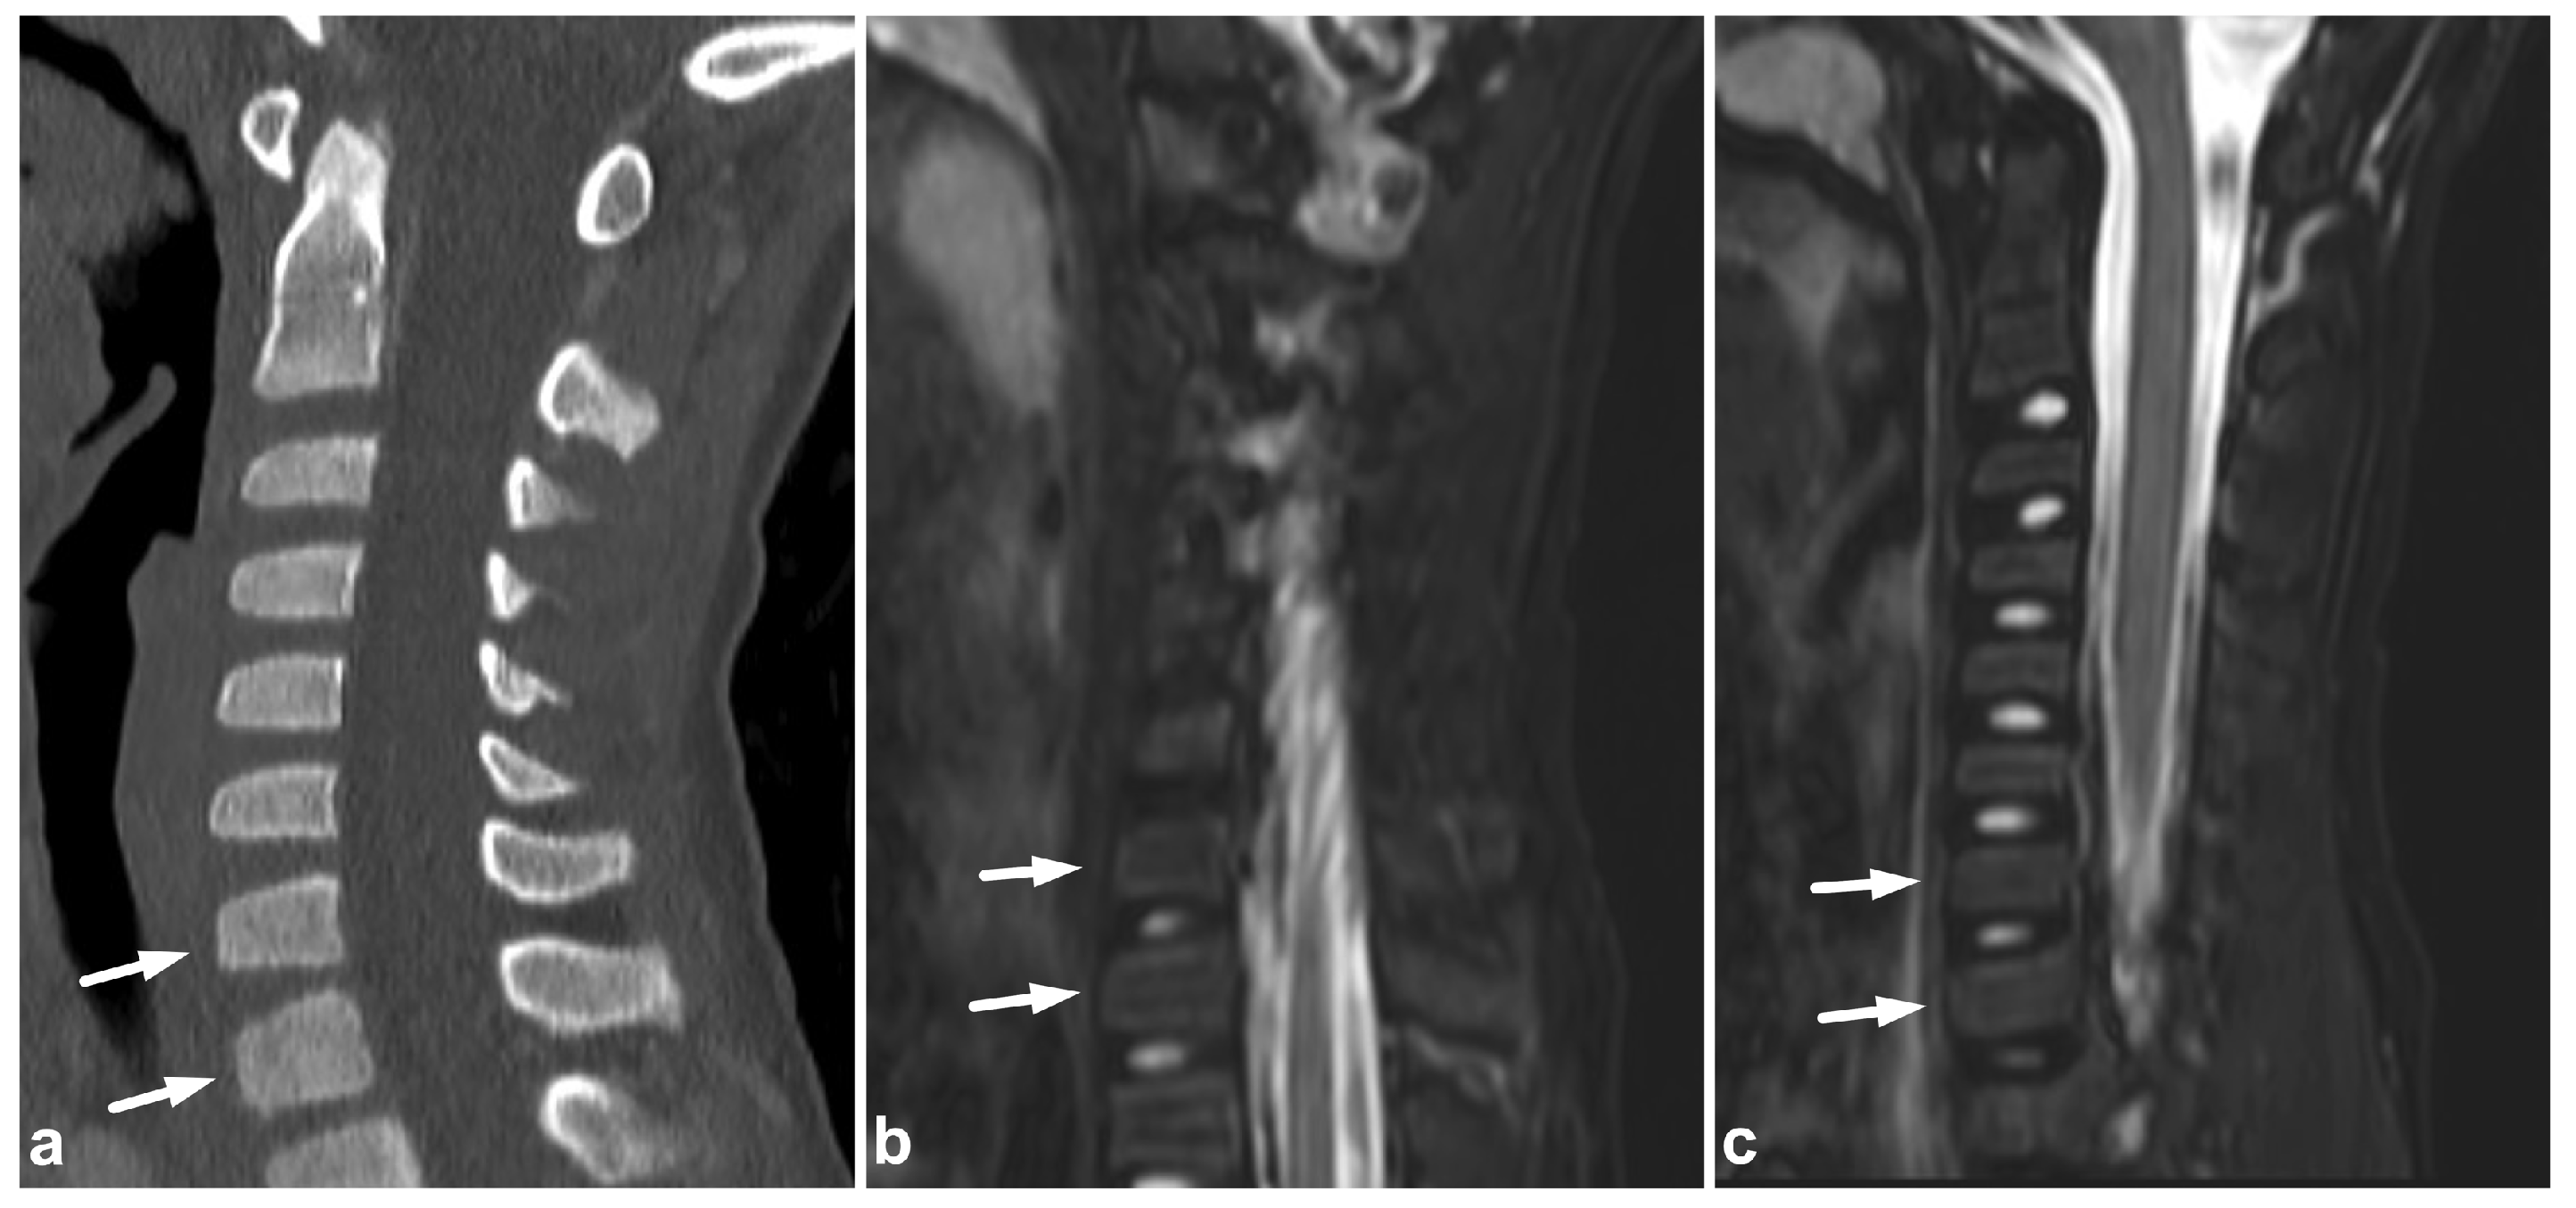

Figure 3.

(a) Sagittal T2-weighted. (b) Sagittal T1-weighted. (c) Sagittal left-sided off-midline T1-weighted. (d) Sagittal right-sided off-midline T1-weighted. (e) Sagittal left-sided off-midline T1-weighted. (f) Axial T2-weighted. (g) Axial T1-weighted. A 2-year-old female, motor vehicle accident. Chance-type fracture through the vertebral body and the posterior arch is seen in L2 (white arrows). L2/3 and L3/4 facet joints are widened and subluxated (black arrowheads). Kyphosis at level L2. Compression fracture in L3 (white asterisk) and contusion in L4 (black asterisk). Posteriorly, there is a longitudinal intradural hematoma (black arrows) and epidural hematoma (white arrowheads). A paraspinal hematoma (curved arrows) and posterior subcutaneous hematoma are also seen.

3.2. Chance Fractures

Pediatric chance fractures are rare high-energy injuries often caused by motor vehicle accidents. The most commonly affected levels are L2 and L3 [19]. CT is crucial for the initial assessment of a potential polytrauma patient. As secondary imaging, MRI can distinguish physeal and discal involvement, ligamentous injuries, and spinal cord injuries in addition to the course of the fracture lines [28,29,30,31] (Figure 3).